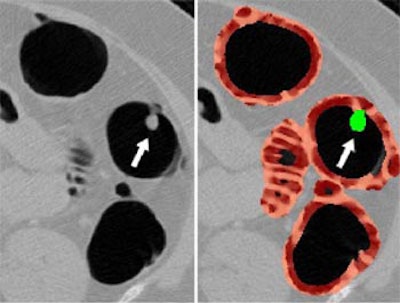

| Left, axial view of a polyp in the descending colon (arrow). Right, display of computer-aided detection (CAD) result for the same polyp. Regions likely to represent polyps, folds, and colonic wall are highlighted in green, pink, and brown, respectively. The polyp (arrow) is correctly highlighted in green by CAD. |

In the volume-rendered endoscopic views, voxels with the shape-index values corresponding to the cap, saddle/ridge, and other classes are colored green, pink, and brown respectively, enabling clear delineation of CAD-detected polyps from other structures.